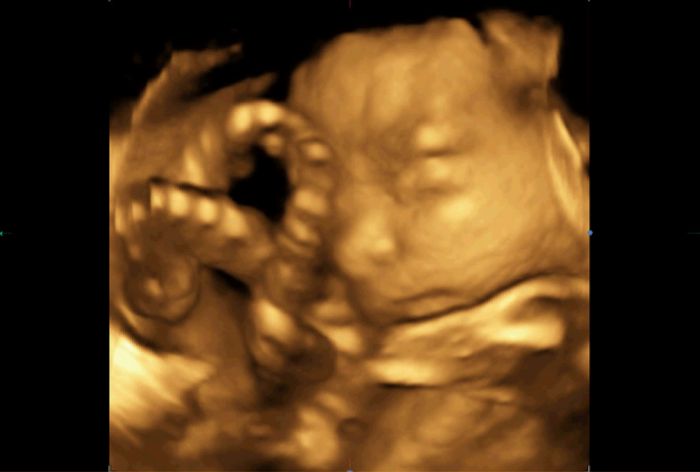

No a minulou středu 3D/4D u mého obvodního gynekologa ( má opravdu dobře vybavenou ordinaci). Nejdřív jsem si myslela, že se nám to moc nepovedlo, páč se nám většinu času schovával za ručičku, ale dle toho, co slyším od ostatních to vlastně byl úspěch

Přikládám fotečky uložené z videa na DVD , které nám dal dr.